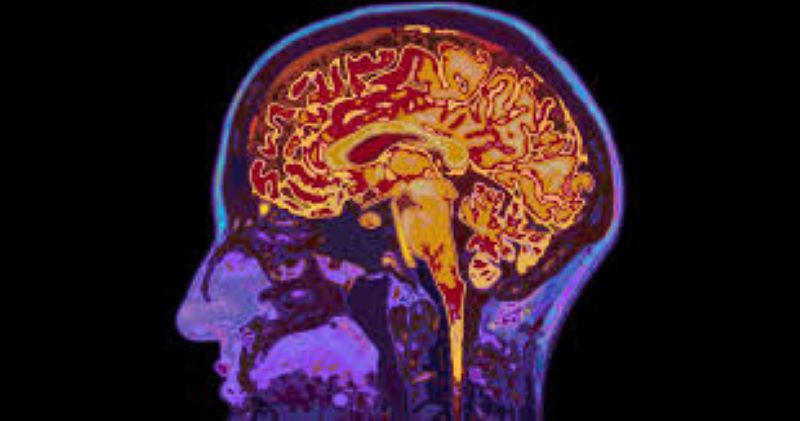

Un reciente estudio publicado en Nature Communications ha sacudido los cimientos de la neurociencia al proponer que los recuerdos no solo residen en el cerebro, sino también en otras células del cuerpo humano.

Este descubrimiento podría revolucionar nuestra comprensión de la memoria, sugiriendo que la capacidad de almacenar y procesar información podría ser un fenómeno compartido por todas las células, no únicamente por las neuronas.